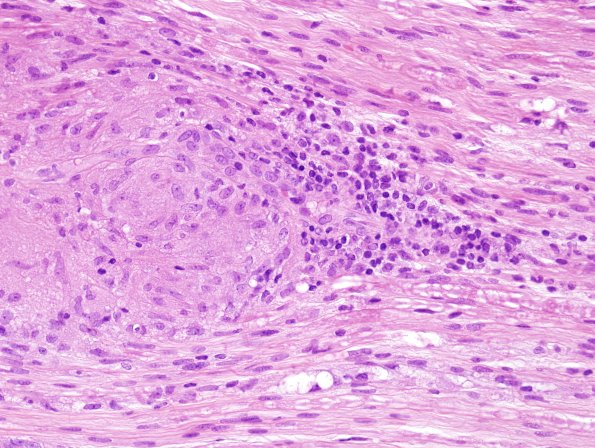

Higher magnification of the edge of a granuloma. (H&E)